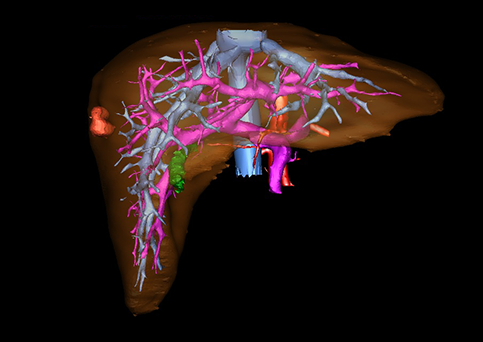

近年来由于数字医学的发展,基于可视化三维重建技术的计算机辅助手术系统极大推进了小儿肝脏肿瘤的精准手术的进步。可以立体透视肝脏解剖、精确掌握肝段的边界、精确测算肝段乃至任意血管所支配的功能体积、准确定位病灶及其与邻近血管的解剖关系,最终对不同手术方案进行比较、筛选和优化。因此,计算机辅助手术规划系统是实现精准肝切除的有力辅助工具,是未来数字外科、精准外科等21世纪外科新理念的重要技术支撑。

计算机辅助手术规划系统具有良好的操作可行性、计算准确性和三维显示效果,可半透明、交互式显示真实的肝内立体解剖关系和空间管道变异,准确计算肝内管道的直径、走行角度,两点间的垂直距离,和任意血管的支配或引流范围等传统二维影像无法获取的信息,有助于实施个体化手术,提高了手术的确定性、预见性和可控性。计算机辅助手术规划系统可直观显示预留肝脏的结构和功能,并可通过虚拟切割功能辅助术者对手术方案进行蹄选和优化,系统评估手术风险和制定对策,改变了部分二维规划的术式和切除范围,使部分二维规划认为不能切除的患者成功手术,提高了手术的根治性、安全性和病变的可切除性,更加符合精准肝脏外科的术前规划要求。详见第11章。

随着计算机技术及影像检查技术的不断发展,以精确的术前影像学和功能评估、精细的手术操作为核心的精准肝切除技术日益受到重视。基于数字医学的计算机辅助手术技术(computer-assisted surgery,CAS)则是实现肝脏精准手术操作的基础。计算机辅助手术系统(CAS)可将术前二维(two dimensional,2D)的CT/MRI影像数据进行三维(three dimensional,3D)重建,建立个体化的肝脏三维解剖模型,清晰显示肝脏内脉管系统的走行及解剖关系,还原病灶与其周围脉管结构的立体解剖构象,准确地对病变进行定位、定性和评估,制定合理、定量的手术方案,实施个体化的肝脏血管取舍分配方案及实施精准肝脏手术。一般认为CAS包括:创建虚拟的患者的图像;患者图像的分析与深度处理;诊断、手术前规划、手术步骤的模拟;术中实时导航。应用本技术后,由于可以更清晰地看出肿瘤的界限,特别是根据肝血管的显影,判断出肿瘤与门静脉及肝静脉的关系以在手术前较准确地估计出手术成功切除的可行性。以往部分根据普通强化CT判断无法手术的病例而被评估为可以成功切除并手术成功。